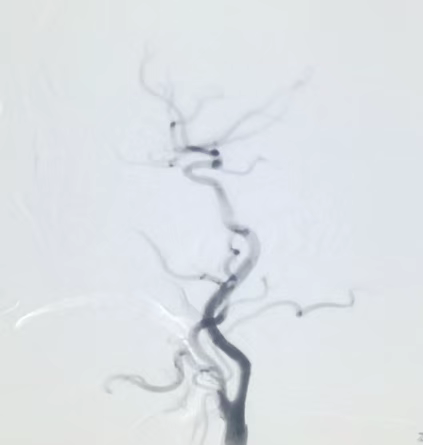

术前DSA示:左侧锁骨下动脉重度狭窄,左侧颈动脉内大量血栓形成,管腔狭窄。

术后DSA:支架置入在位,狭窄血管恢复正常血流。

术前DSA示颈动脉重度狭窄

术后DSA见颈内动脉显影清晰,血流灌注良好